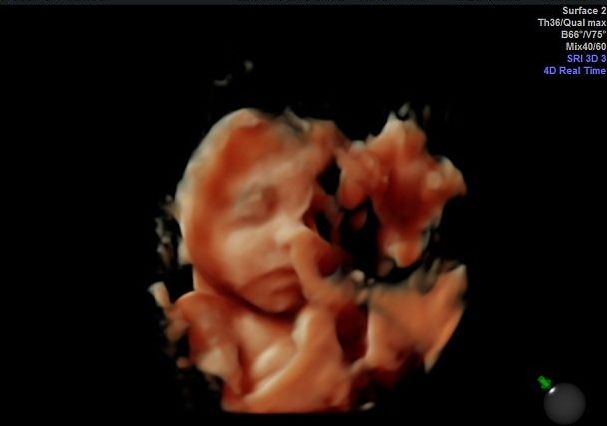

I nearly had a heart attack at the ultrasound because it look liked there wasn't any fluid!! It was the first thing I noticed, and I almost started crying, but the tech giggled and said not to worry. It looked that way only because baby had jammed herself into my left side (she does that often), and all the fluid ended up over on the right side. Whew.

We actually transferred to a midwife and birth center since then (I love them already!), and went to one of their recommended specialists. They were covered under our insurance, and we only had to pay $50 for the ultrasound. We got some really cool photos, too.